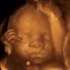

Ultrasonografia 3D

Przykładowe zdjęcia 3D z aparatu USG.